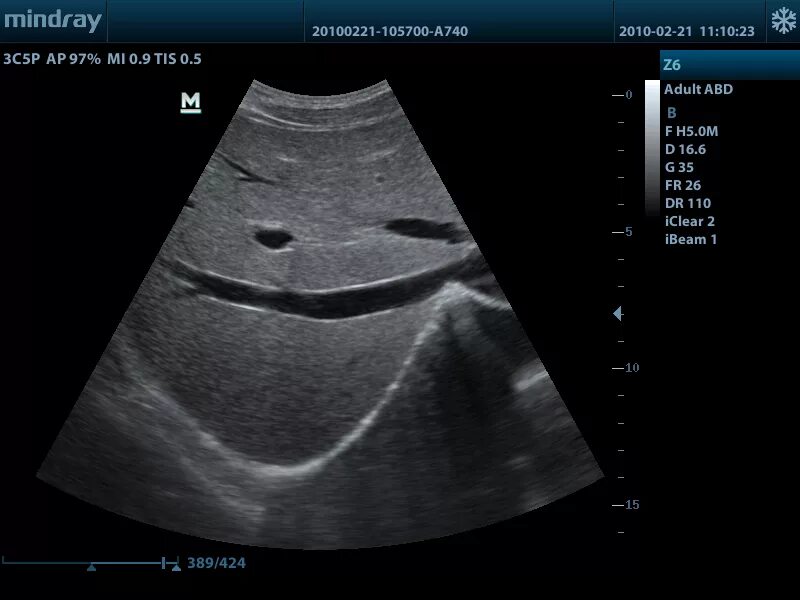

Экран аппарата узи